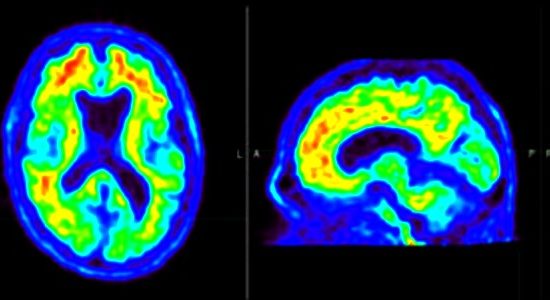

भारतीय शोधकर्त्ताओं ने अल्जाइमर के कारण भूलने की आदत रोकने के नये तरीकों का पता लगाया है। अल्जाइमर रोग (Alzheimer disease) का इलाज भारत में विकसित करने का बहुत महत्व है। भारत में 40 लाख से अधिक लोग अल्जाइमर रोग (Alzheimer disease) से जुड़ी भूलने की आदत के शिकार हैं। कारण…